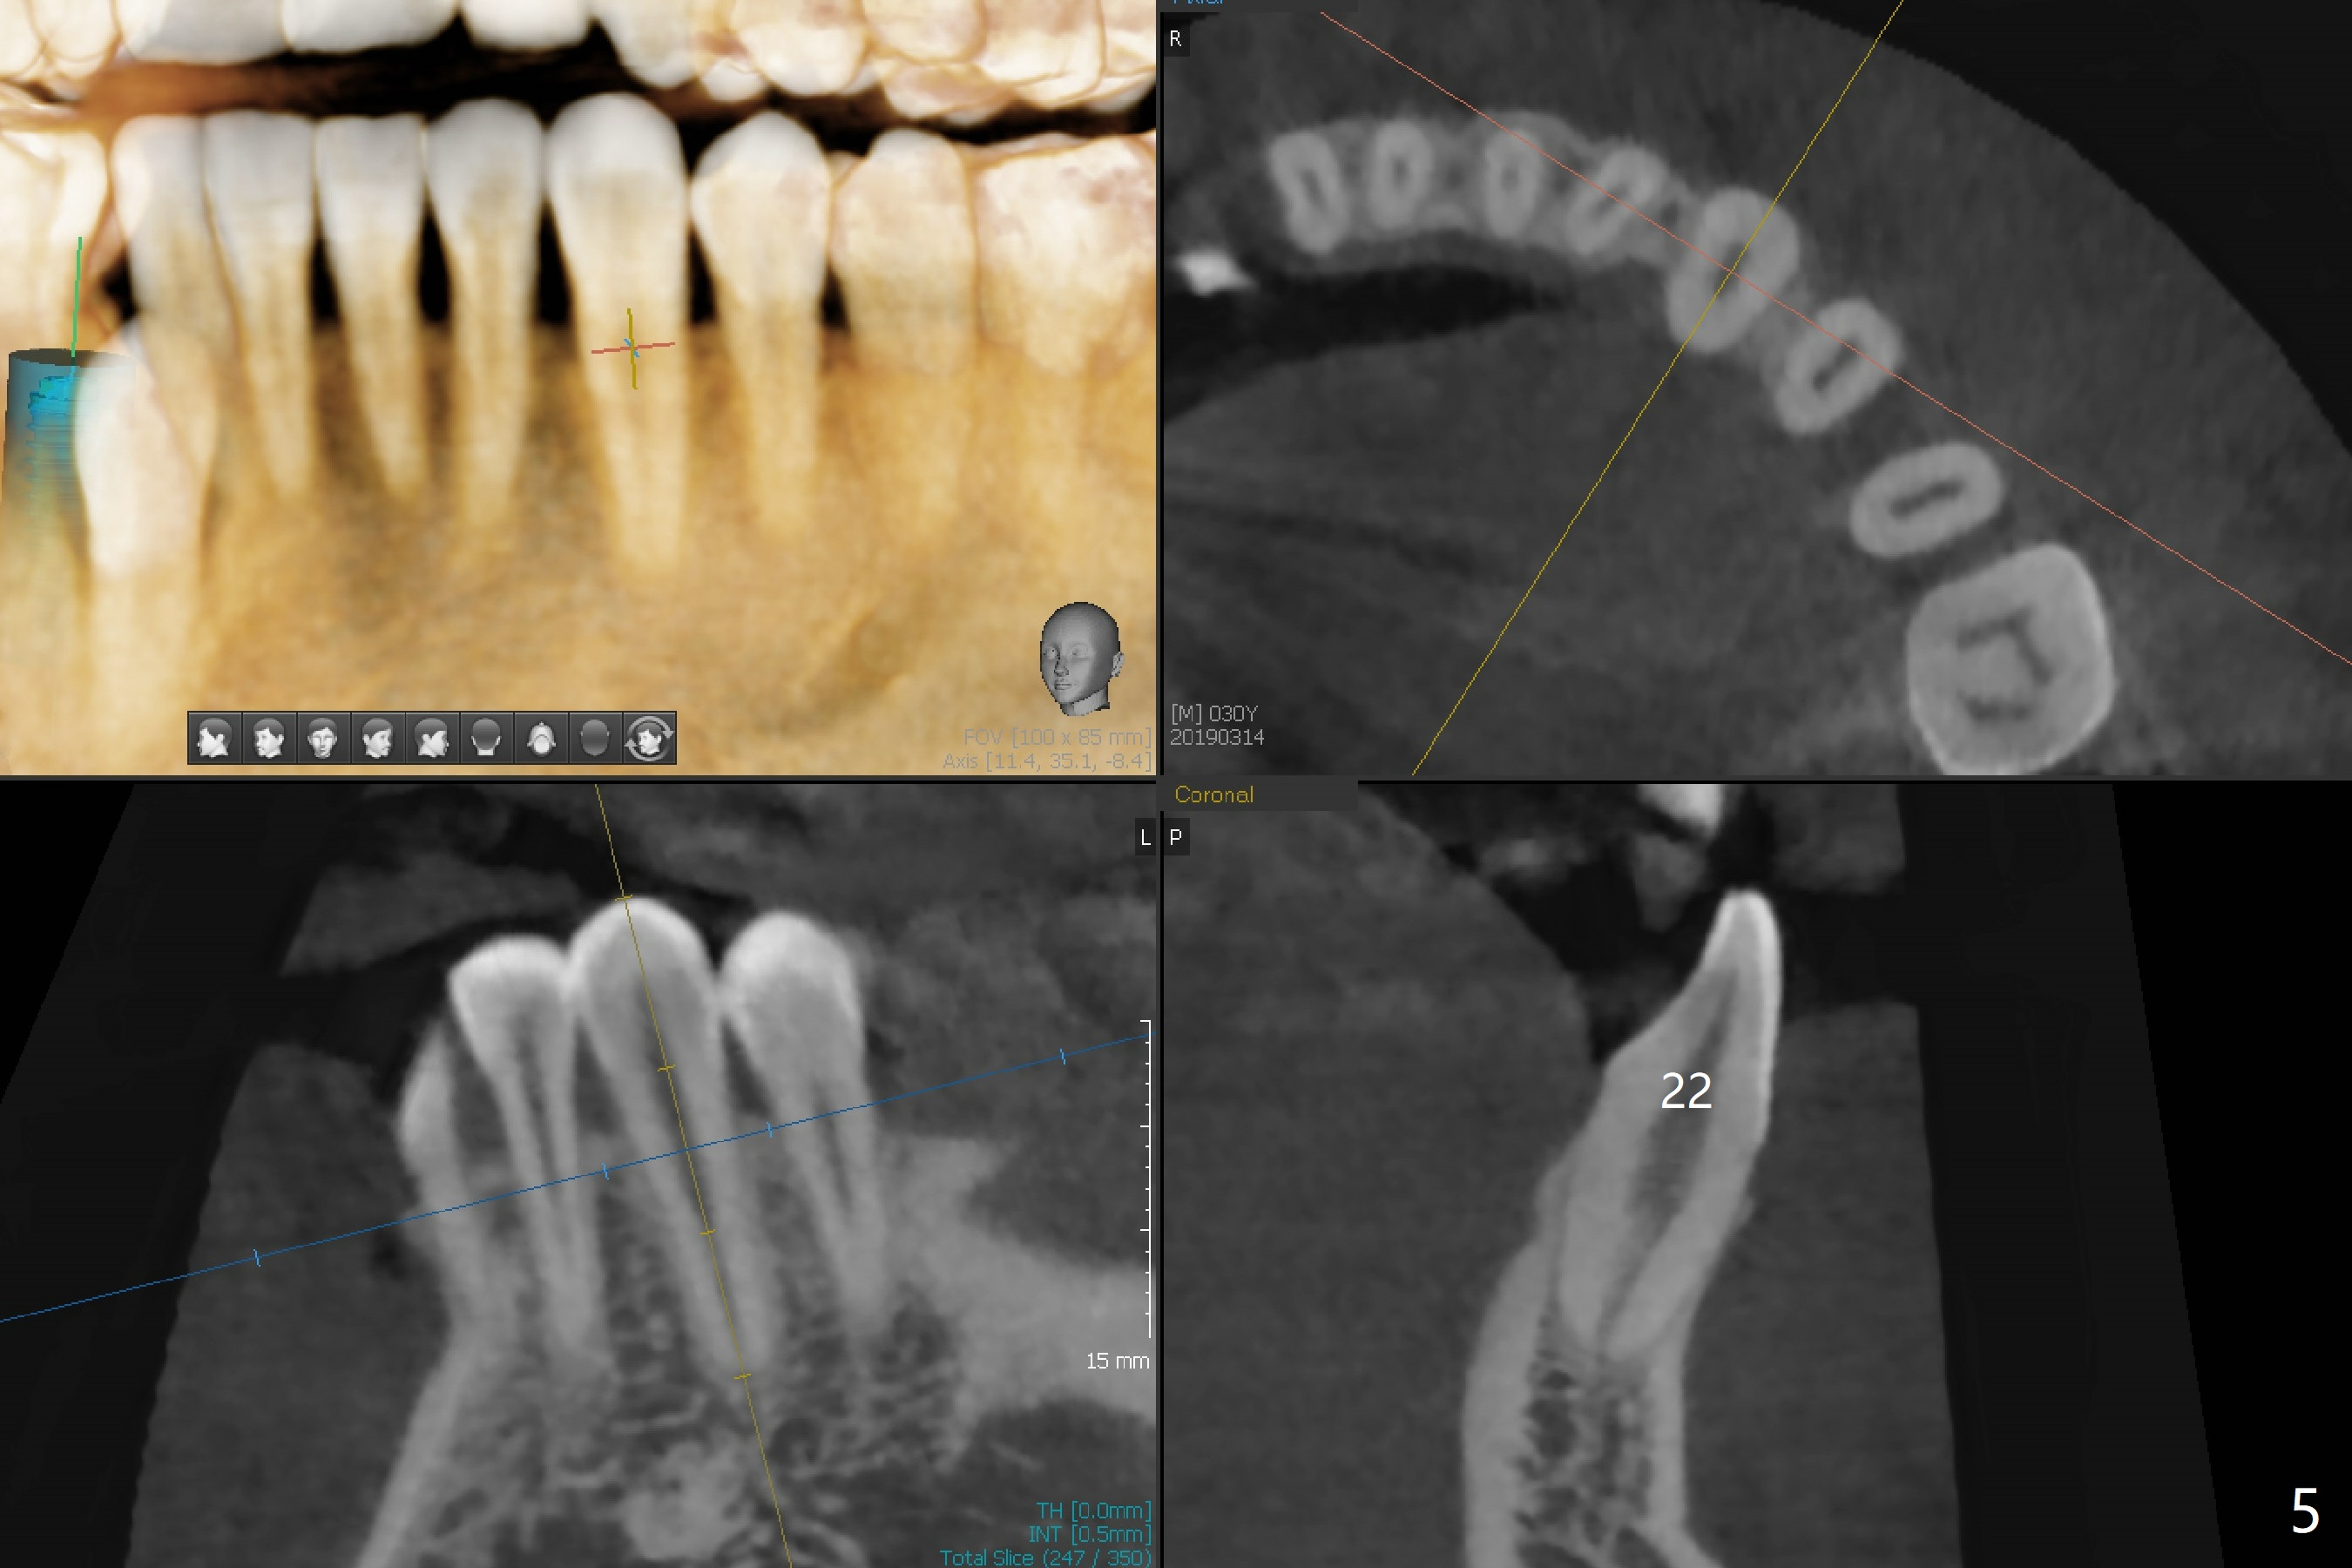

A 30-year-old man requests orthodontic extrusion of the impacted lower right canine and implant at the next site (Fig.1). Since the canine rotates with wider mesiodistal width of the crown (Fig.2 red line), the implant should be smaller and placed distal (Fig.2 red arrow). The extrusion will gain the bone to the distal surface of the lateral incisor (Fig.2, 3*). In fact the tooth #27 is malformed in that the root is split (Fig.4, as compared to the tooth #22 (Fig.5)). Surgical guide will be used for precision.